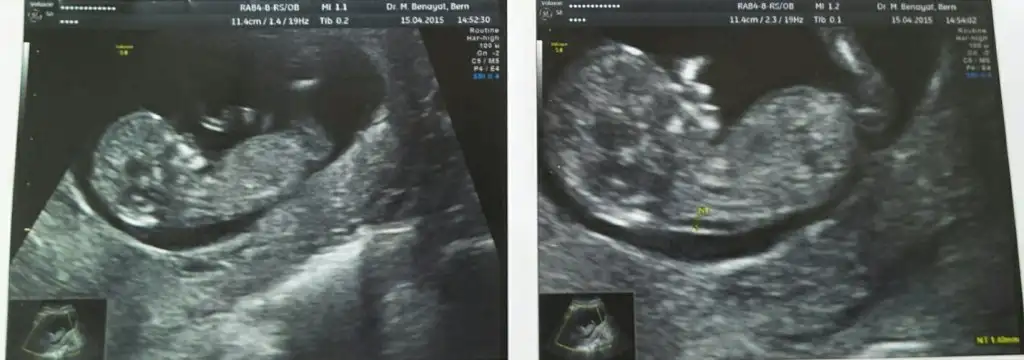

Bir önceki ultrason görüntüsünde bazı arkadaşlarımız bacak mı, pipi mi diye kararsız kalmıştı, bazı arkadaşlarımız kız demişti. Doktorum da kız demişti.

Bugün tekrar doktordaydım ve videoya aldık ultrason anımızı. Eve geldikten sonra çektiğimiz videoyu izledim. Doktor çok büyük ihtimalle erkek demeden hemen evvel ekranda bu görüntü var.:KK68: Sanırsam bacak arası ve pipisi de orada :KK48: O kadar büyük olur mu pipisi :KK48:

Anaaa :)) bebis erkegim diyoo annesiii doktoe hicmi bisey demedi bariz pipi ortada.. Sen böyle demişsin canım. Tebrikler valla resmen pipi ortadaymış :KK48:

Valla doktorda fark etmemiştim ama gelince gördüm ben de. Baya açmış. Bir de uyuyordu o zaman. Eminim doktorda beklemiyordu. Çünkü cinsiyet sordum, 16.haftada dedi. Sonra anlatmaya başladı işte, burası burnu, çene kemiği, burası alnı, bak elleri dedi. En son bacakları diyor ve sessizlik oluyor :KK48: Peşinden de çok büyük ihtimal erkek diyor :KK48: